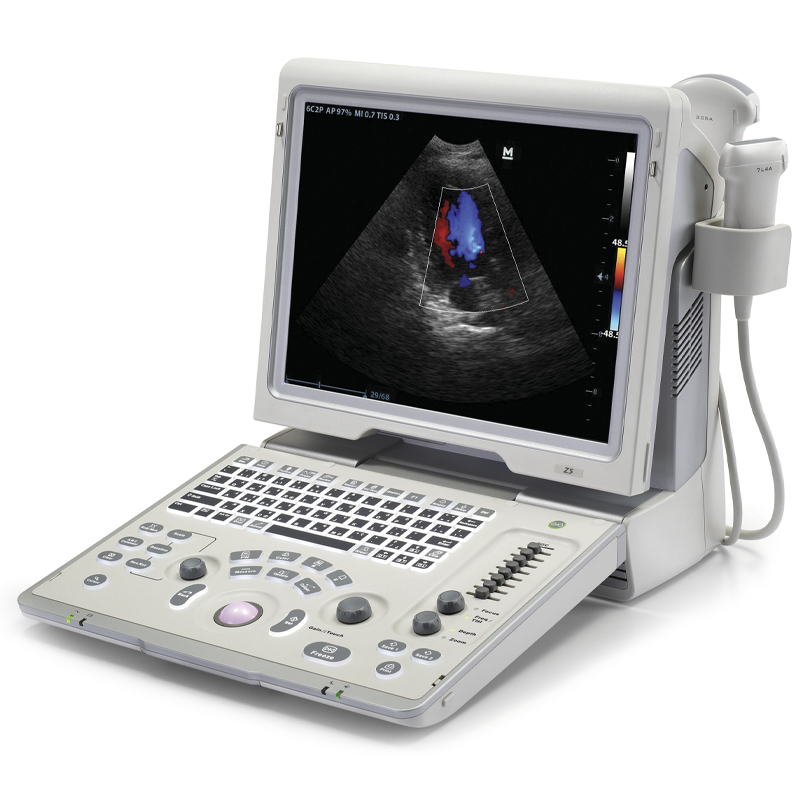

УЗИ аппараты российского производства: обзор и характеристики